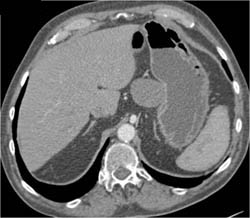

Antral Cancer